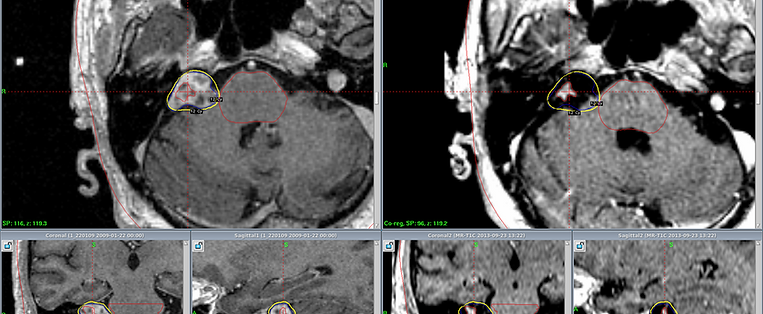

Невринома уха

Невринома уха 111 фотографий